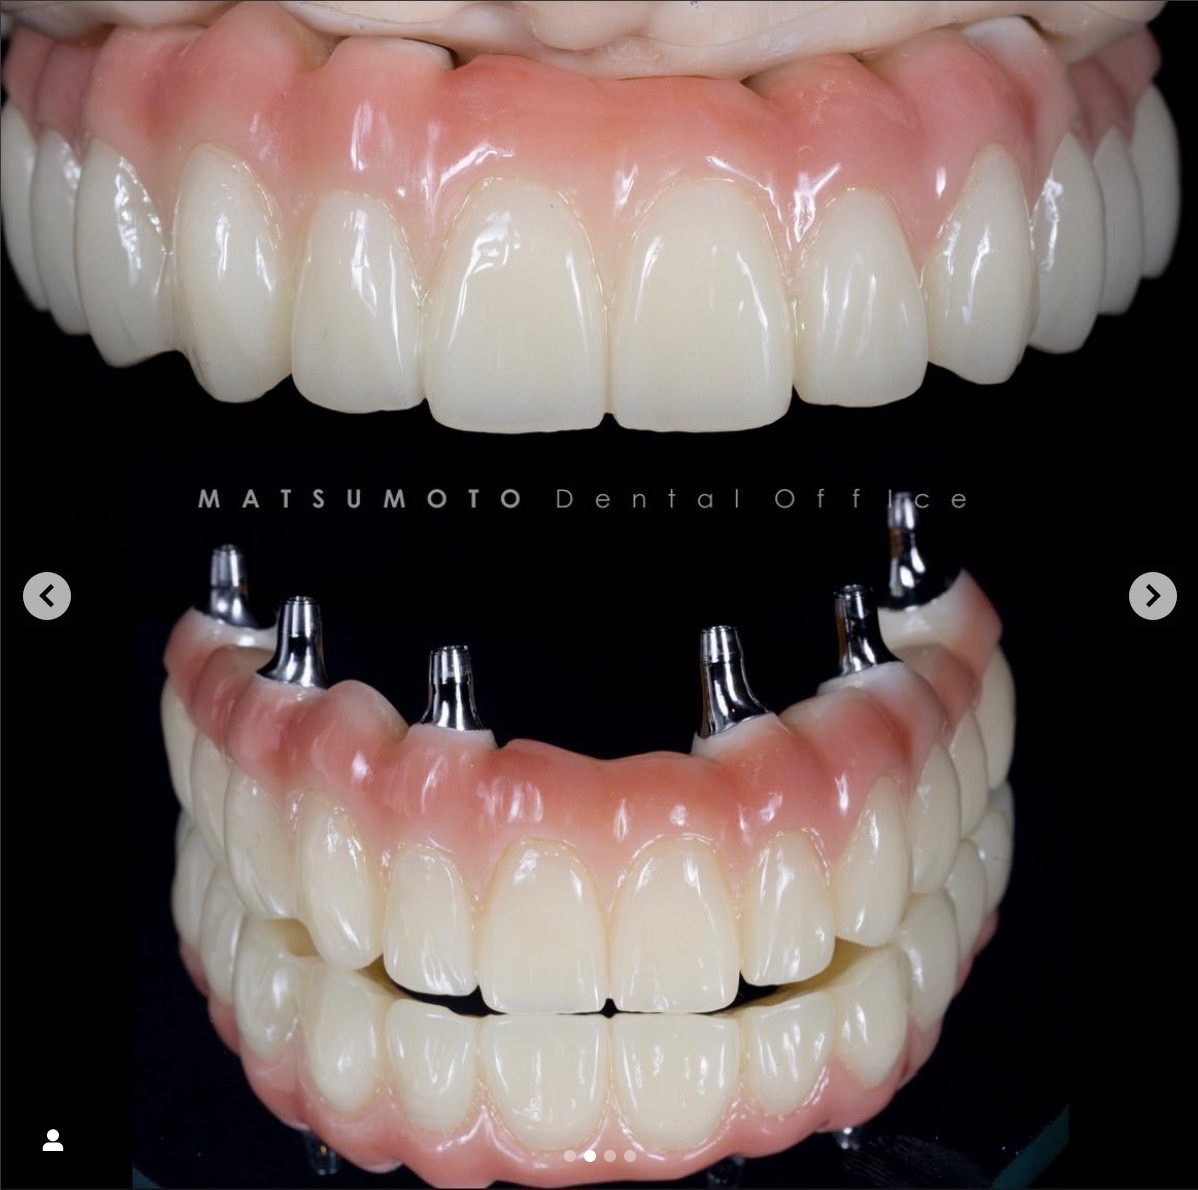

オールオンフォー(All-on-4)治療法では、手術当日に固定式の仮歯を装着することができます。この方法では、頬骨に特殊な長めのインプラントを使用し、しっかりと固定するため、手術当日に見た目と機能の両方を回復することが可能です。

下顎には4本、上顎には4~6本のインプラントを使用し、

即日に機能と美しさを取り戻すことが可能な画期的な治療法です。

従来のインプラント治療では、多くの歯を失っている場合、複数本のインプラントを埋め込む必要がありました。そのため、全ての治療が完了するまでには時間がかかり、途中で入れ歯を使用することが不可欠でした。しかし、オールオン4(4本)インプラントでは、4本もしくはオールオン6(6本)のインプラントだけで手術が完了します。

オールオン4インプラント治療は、歯がボロボロの方や総入れ歯の方にも適しています。手術当日に噛むことができる歯を取り戻し、入れ歯の不便さから解放されます。仮歯の装着により自然な見た目と機能を即日に提供します。